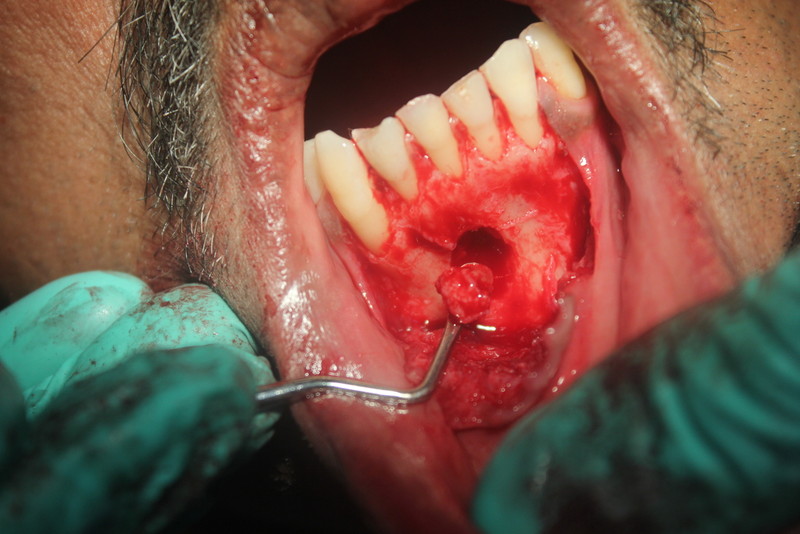

Apicoectomy